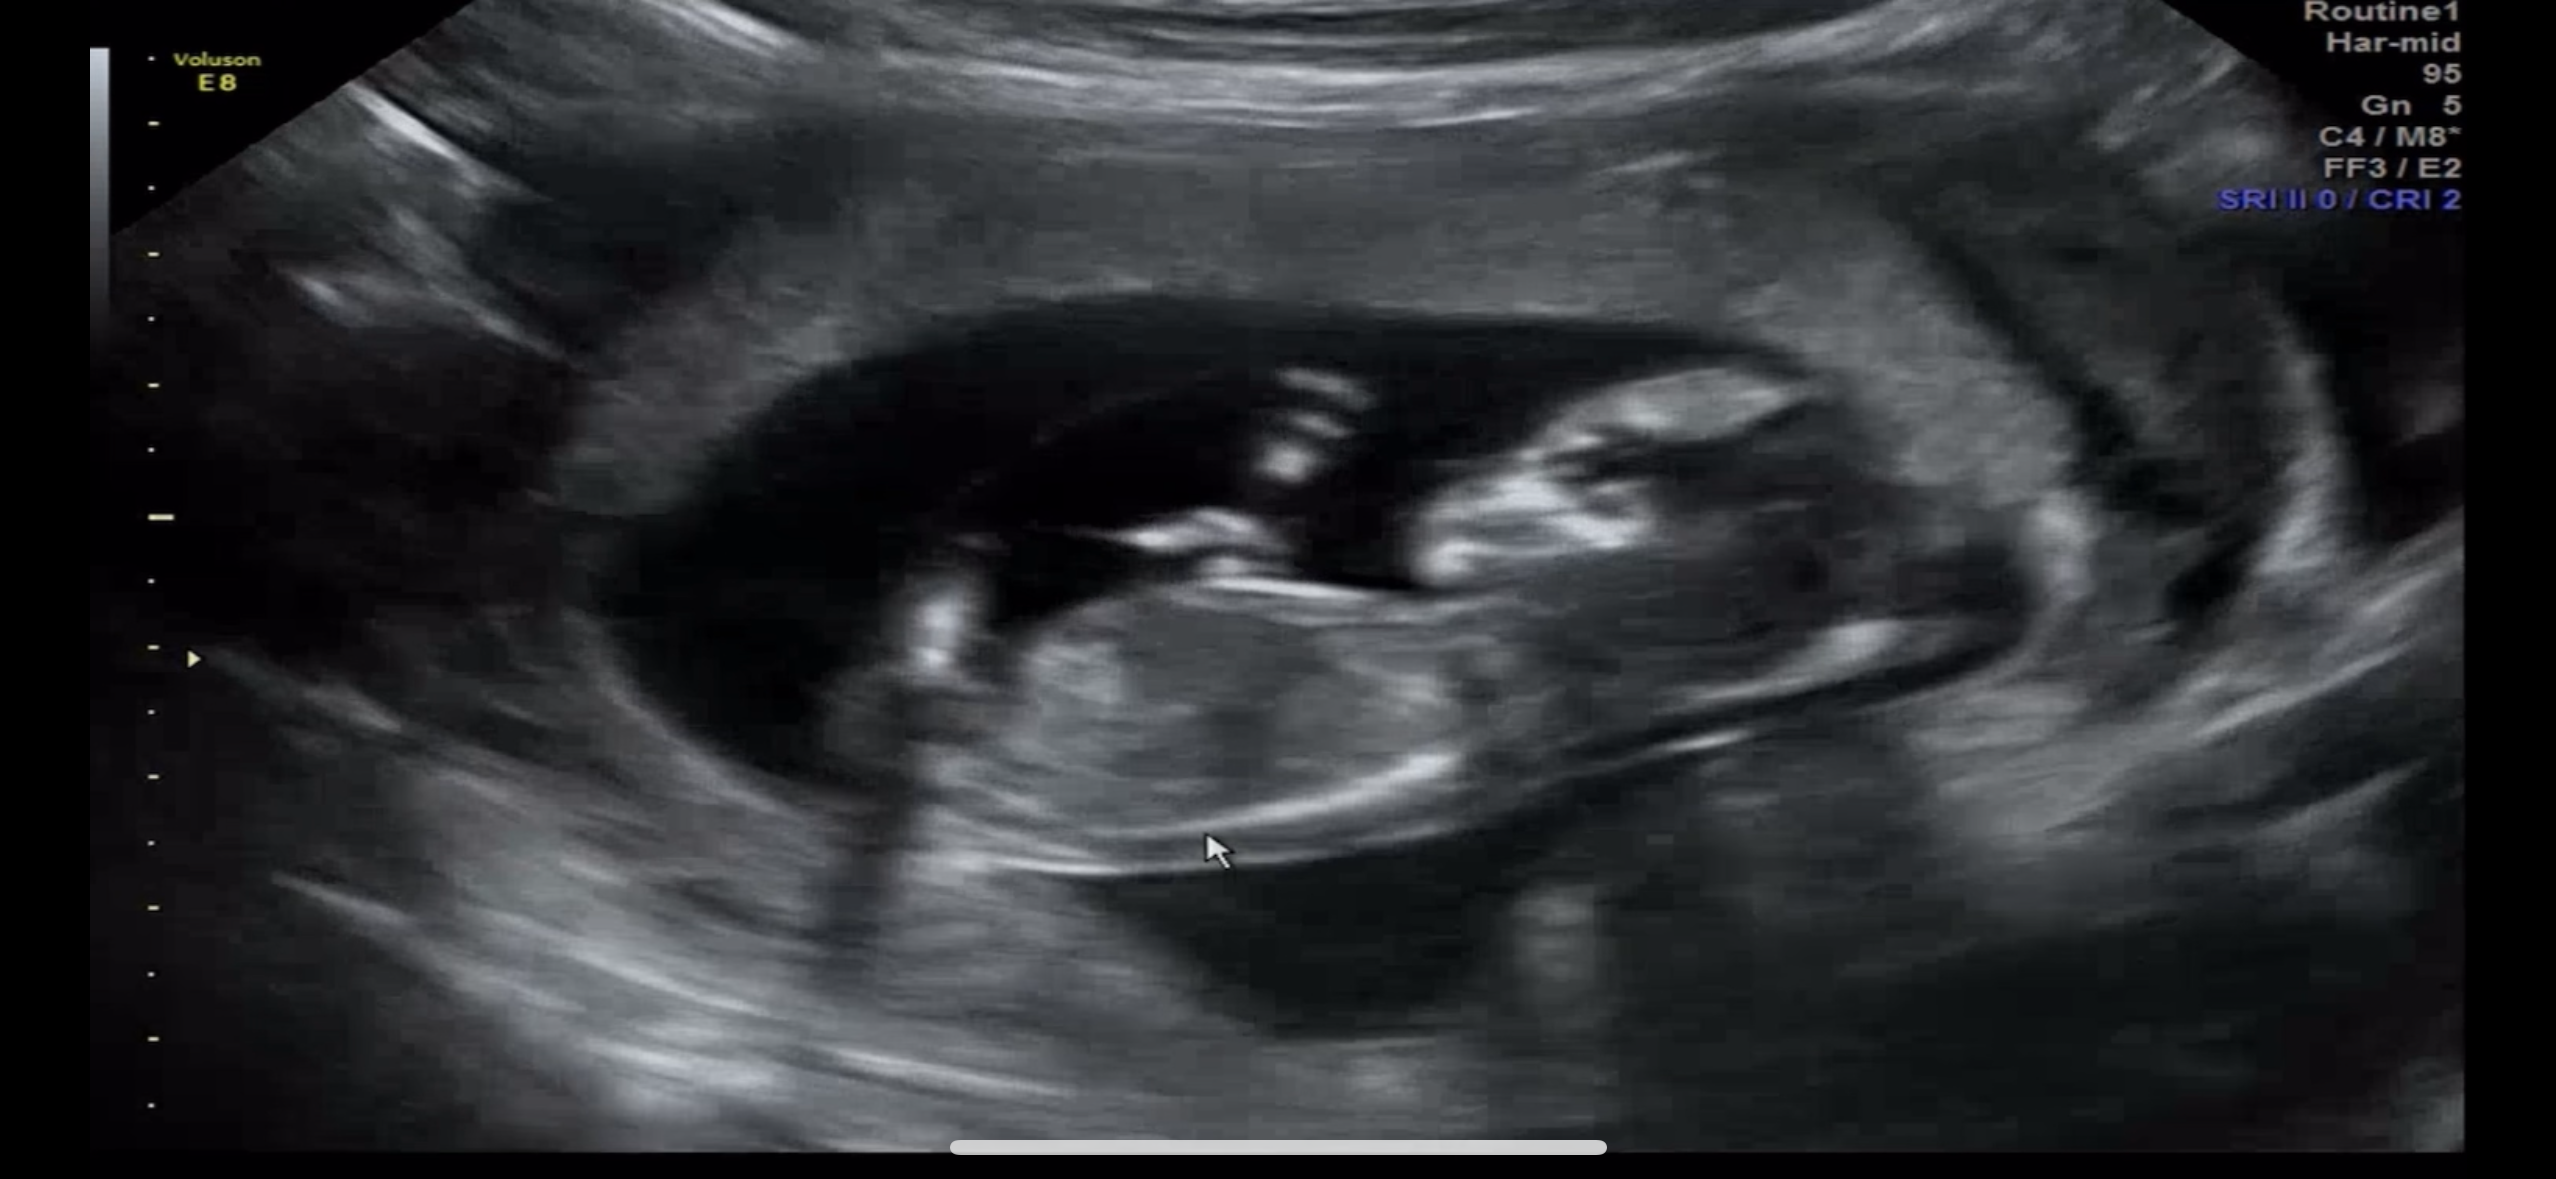

12주 아기가 뭘 뱉어요..!?

오늘 12주 1일 초음파 찍고 왔는데 아가가 뭐를 뱉네요??? 선생님한테 여쭤봐도 잘 모르겠다고 하셔서.. 뭘 뱉은걸까요?? 저기 머리 왼쪽에 동그란걸 뱉어요ㅜㅎㅎ